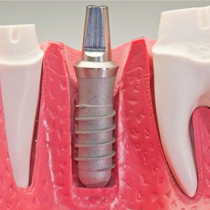

DIENTESIMPLANTES.COM Es una clínica dedicada a la Odontología, Rehabilitación oral e Implantología. Dando así una respuesta a las expectativas de nuestros pacientes.

Contamos con 20 años de experiencia en nuestra labor, lo que nos permite desarrollar procesos integrales en todo el campo de odontología rehabilitación oral e implantología, como consecuencia de ello vemos las expresiones de felicidad de nuestros pacientes al recuperar una sonrisa natural.